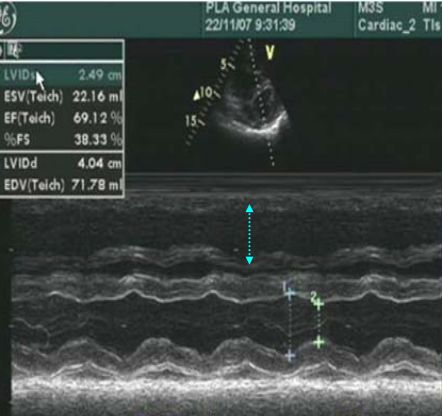

超声心动图

右心衰:右室大,左室小,左室呈D形,少量心包积液

Rudski LG, et al. J Am Soc Echocardiogr 2010;23:685–71